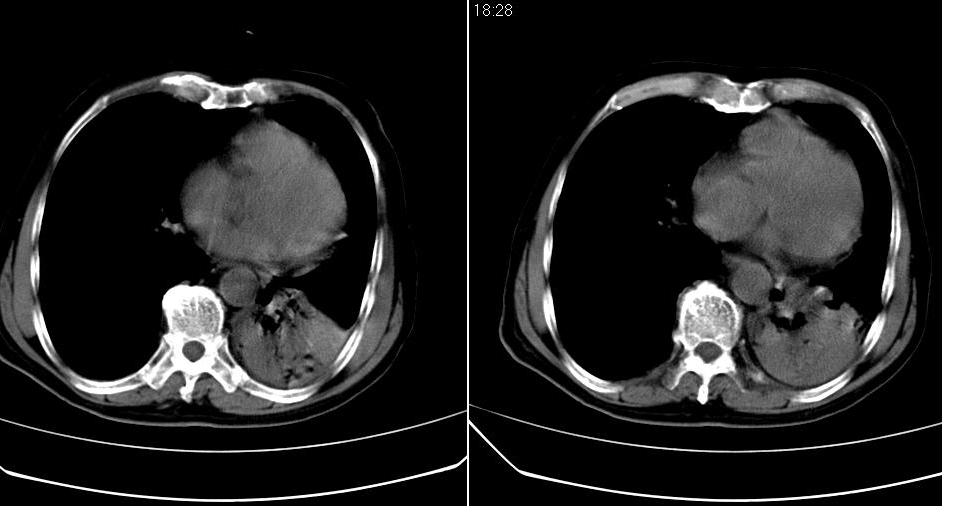

左下肺体积缩小,密度增高,见片增密影。边界模糊,见支气管充气像,肺门纵隔无异示,心脏气管左移,左侧胸腔少量积液。考虑肺部感染伴部分肺不张[有脑梗塞病史坠积性肺炎可能]

1、左肺下叶后基底段炎症并膨胀不全。

2、左侧胸腔积液。

左下肺体积缩小,密度增高,并见大片状致密影,边界模糊,其内见支气管充气像,肺门纵隔无异常,心脏气管左移,左侧胸腔少量积液。考虑:左肺炎性病变伴不张。

左肺下叶感染,肺膨胀不全,左胸腔积液,不能排除结核性病变